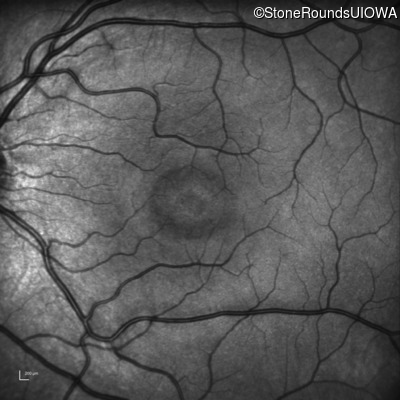

XL Retinoschisis (IIIB1)

XL Retinoschisis (IIIB1)

This 6 year old boy first experienced difficulty reading and seeing the blackboard at age 5.

| XL Retinoschisis | RS1 | Pro192His CCC>CAC | XL |